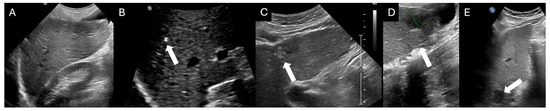

3. Diagnosis of Chronic Liver Disease and Cirrhosis

6. Abdominal Ultrasound